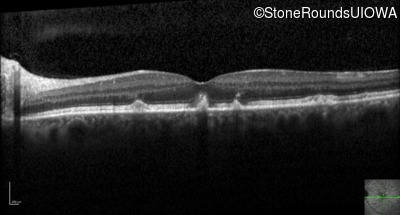

Optical Coherence Tomography - Right - 20/20 -1 sc

Exemplar / OCT Stack

OCT Stack